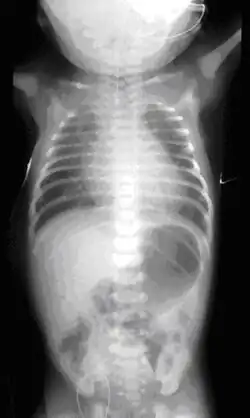

- une sonde « naso-gastrique » très fine peut être introduite dans l'œsophage du nouveau-né. Si elle est bloquée après quelques cm, c'est qu'il y a atrésie[3].

Dans presque tous les cas une anomalie de la trachée est associée, et dans la moitié des cas environ[3], l'atrésie de l'œsophage est associée à d'autres malformations, comme dans le cadre du syndrome de VATER (présent dans 10 % des cas[3]) ou de VACTERL. Il convient donc de rapidement rechercher activement d'autres malformations associées qui peuvent toucher le cœur (dans 30 % des cas), mais aussi le squelette (25 % des cas), les reins, les membres, le système digestif (25 % des cas) ou urinaire[3].... Une échographie et une radiographie de l'abdomen confirme le type d'atrésie et des examens complémentaires portent notamment sur le cœur (échocardiographie) et l'anus (une sonde recherche une éventuelle perforation)[3].